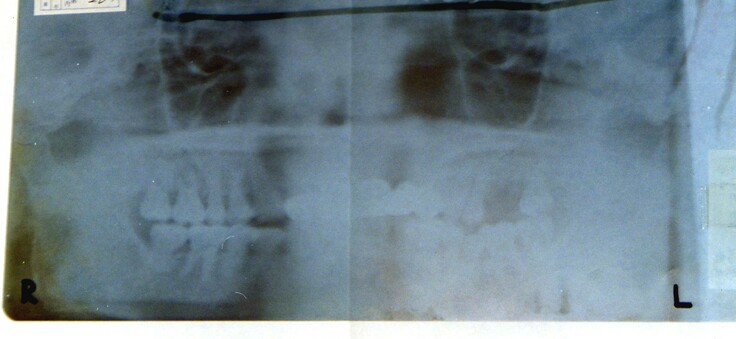

◎ポイント1◎証拠のレントゲンフィルムは偽造されていた。

1980(昭和55)年8月13日、太宰府近くで発見された身元不明の白骨遺体がS氏のものだとする最大の証拠は、歯科レントゲンの写真です。 レントゲン写真は裏表が分かりにくいので、S氏が生前撮ったレントゲン写真には、担当医が赤いマジックで、「右」「左」と記入していました。 しかし、裁判所に証拠品として保管されているレントゲンフィルムには、赤マジックの「右」「左」は記載されておらず、黒で「L」「R」と記載されたものでした。証拠のレントゲンフィルムが差し替えられているということになります。

(赤マジックの「右」「左」はなく、黒で「R」「L」と書かれたレントゲンフィルム)

また、証拠のレントゲンフィルムに、もともと書かれていたはずの赤マジックの「右」「左」は記載されておらず、黒で「L」「R」と記載されていたことについては、裁判所は、鑑定に用いられた際に鑑定人が赤マジックを消したのだろう、と述べました。

また、レントゲンフィルムの鑑定人は、自分たちがマジックを消すなどすることはありえないと述べています。